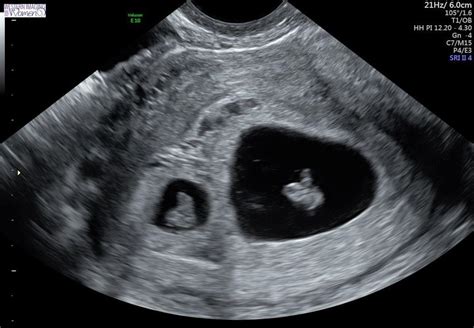

La confirmación de un embarazo gemelar suele realizarse mediante ecografía en las primeras semanas. Las ecografías tempranas son emotivas, permitiendo visualizar las bolsas gestacionales y los embriones.

A partir de las 8 semanas, el tocólogo puede identificar el tipo de embarazo gemelar mediante la observación de signos ecográficos:

- Signo de la T: Indica que los bebés comparten placenta (monocoriales).

- Signo Lambda: Aparece cuando cada gemelo tiene su propia placenta (bicoriales).